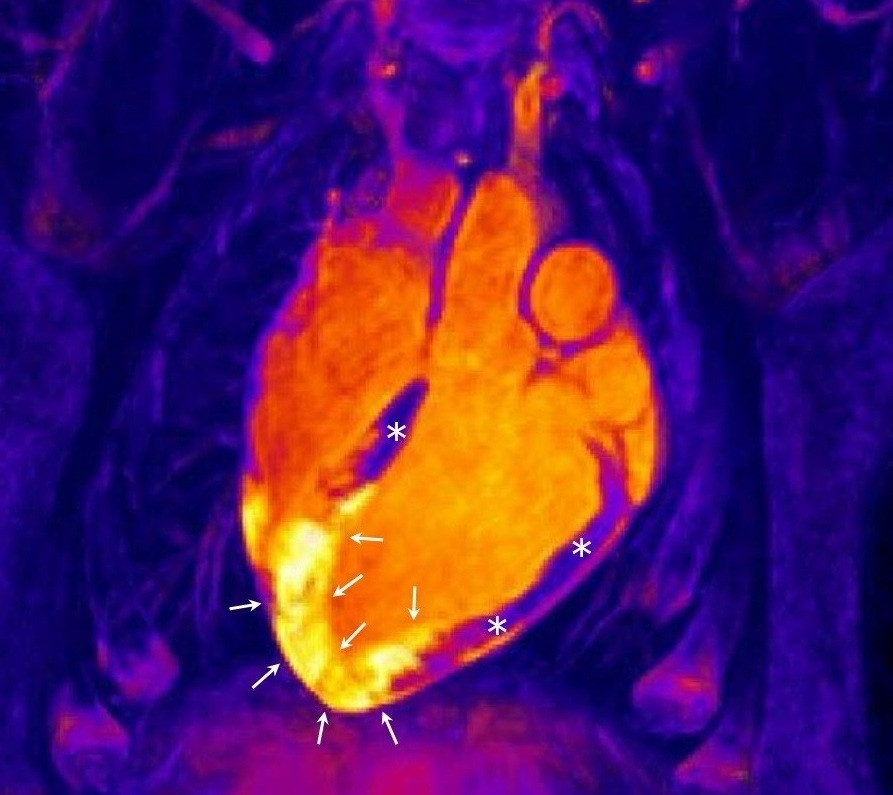

Hace dos años este mismo equipo publicó una serie de trabajos en un modelo experimental donde se cuestionaba este viejo dogma pero en este trabajo, liderado por el cardiólogo Borja Ibáñez, han usado la tecnología de resonancia magnética más avanzada para demostrar que el corazón humano responde con dos reacciones edematosas muy bien diferenciadas y separadas en el tiempo.

Tras la demostración en 2015 de que existía una reacción inflamatoria bimodal en animales de experimentación, quedaba por demostrar lo más difícil, que en pacientes también ocurre esta reacción tan peculiar del músculo cardiaco.

El descubrimiento de la reacción bimodal del corazón humano, hace "replantearse" el momento en el que los ensayos clínicos deben realizar una resonancia magnética para cuantificar el daño irreversible de los pacientes y el efecto de terapias aplicadas para reducir este daño, según los autores.

"Hasta ahora existía una visión liberal y estos estudios de imagen cardiaca se realizaban en cualquier día post-infarto. Estos nuevos trabajos nos muestran que las resonancias magnéticas con este objeto deben de realizarse entre el día 4 y 7 post-infarto, momento en el que la segunda onda inflamatoria/edematosa es prominente y ocupa toda el área que estuvo sin riego sanguíneo durante el infarto", ha explicado Ibáñez.